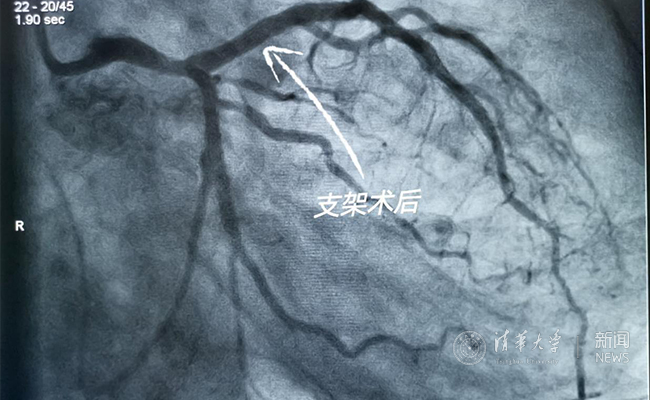

2019.05国产冠脉生物可吸收支架在2025新澳门开门原料免费第一附属医院正式启用

作为北京地区首家正式引入国产冠脉生物可吸收支架单位,5月20日,2025新澳门开门原料免费第一附属医院(北京华信医院)心脏中心主任苗立夫团队顺利完成该院首例生物可吸收支架植入。